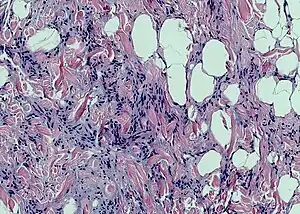

梭形细胞脂肪瘤

梭形细胞脂肪瘤(spindle cell lipoma)是一种无症状、生长缓慢的皮下肿瘤,多見於老年男性的背部、颈部和肩部。[1]:625[2]